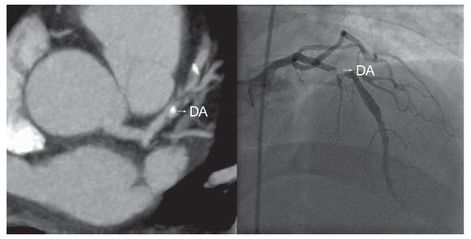

ANGIO TAC CORONARIA: Un avance en el diagnóstico cardiológico

“El Angio TAC permite evitar la coronariografía invasiva con finalidad meramente diagnóstica en un elevado número de casos”  “La Dra. Teresa Rius, Directora de la Unidad de Angio TAC, posee una experiencia acumulada de más de 400 exploraciones con esta tecnología”